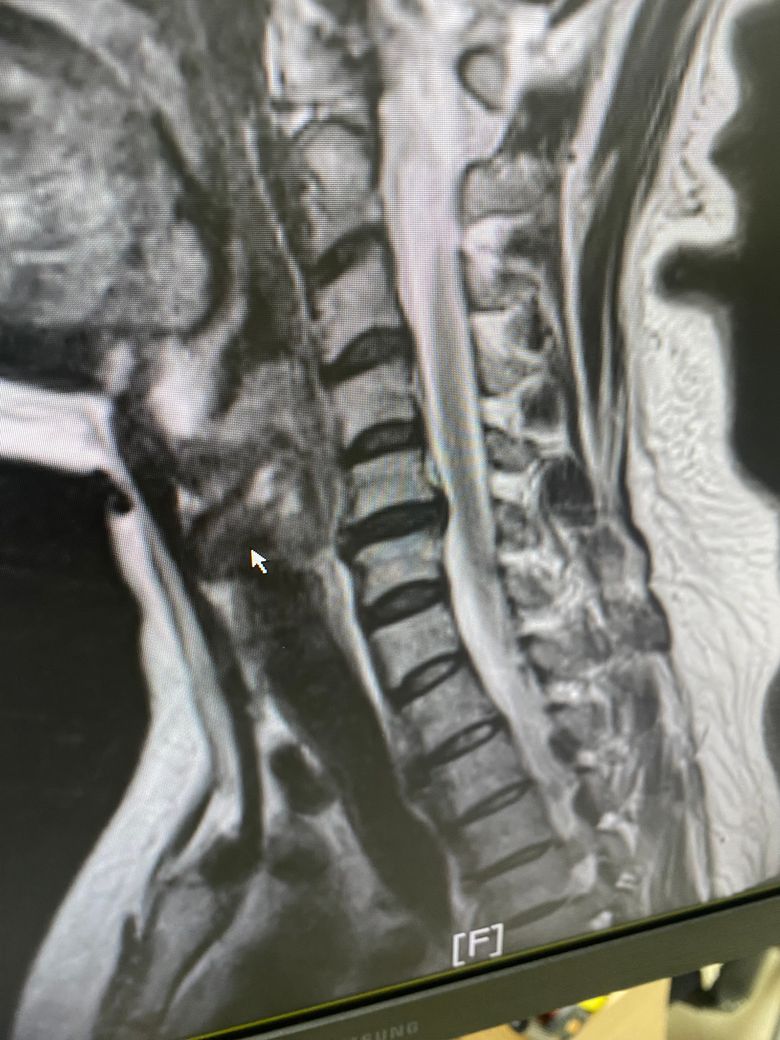

오늘 진료 보는데 두번째 사진도 보여주셨어요

• 2번 째 사진

근데 너무 튀어나온거 같아 심히 걱정입니다.

사실 여러 환자분들 보았지만, 그렇게 심하진 않습니다. 병원에서는 현상 상태를 말하니 디스크라는 표현에 환자분들이 걱정을 많이 하는데, 지금 그렇게 심해보이진 않습니다. 그리고 신전운동 할때 뻐근한거는 제 생각인데 목이 구조가 현재 일자목인데, 등도 좋아보이지 않습니다. 등도 굽어계시거나 평평하게 일자로 되있으실거같은데, 그런 목 등 에 대한 움직임 개선이 좋아 보일거같지 않습니다.

일자목에 약간의 역c커브형태로 보여집니다 맥킨지 신전자체가 찌릿하거나 불편함이 가중되면 일단 중지하시는게 좋고, 약물치료와 더불어서 운동치료 가능한 병원 가셔서 운동도 같이 해보시는게 좋겠습니다. 견갑 위주의 운동 + 맥킨지 운동을 각도를 줄여서 한다거나 하는 식의 변형이 도움이 되겠습니다

• 올리신 사진 세 장만 가지고 정확하게 어떻다 이야기 하기는 어렵습니다만, 디스크가 명확하게 돌출이 되어 있기는 하지만 신경을 누르는 정도가 딱히 심해 보이지 않습니다. 해당 사진들만 보았을 때에는 심각한 수준의 디스크로 보이지는 않습니다.